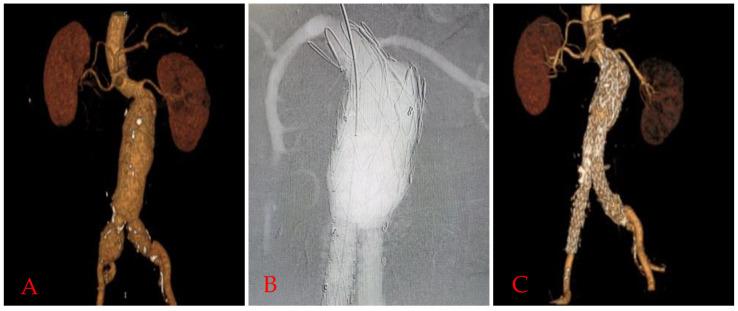

The funnel technique, the hybrid assembly of a thoracic and abdominal aortic endograft, is advantageous for frail patients where efficient oversizing is not possible for infrarenal wide aortic necks over 34 mm. We sought to determine the advantages and disadvantages of the Funnel-endovascular aneurysm repair (EVAR) technique using 60 mm length thoracic endograft.

This retrospective study included 22 patients, all frail with high comorbidities, who were operated on with the Funnel technique using the 60 mm Lifetech Ankura thoracic endograft, in 7 urgent and 15 elective cases from January 2018. There were no exclusion criteria except having an age 60 years. Primary endpoints were the technical success and early mortality and morbidity; secondary endpoints were late outcomes such as endoleak, migration, late open surgical conversion, successful sac shrinkage, and enlargement at the infrarenal aortic neck diameter.

The patients' mean age was 72.6 7.3 years (62-86 years), with a mean aneurysm diameter of 83.2 16.8 mm and mean infrarenal aortic diameter of 38.7 2.4 mm. There was no early mortality. Technical success was 100%. 21 standard bifurcated and one aorto-uni-iliac abdominal endograft were deployed. The mean fluoroscopy time was 14.3 5.2 minutes. Mean follow-up was 32.8 19.6 months, with no endovascular complications. There was no Type-1a or Type-3 endoleak, migration, infrarenal aortic neck diameter enlargement, or aneurysm sac enlargement. During the follow-up, three patients died, but there was no aneurysm-related mortality.

Funnel-EVAR is effective and safe for patients with a wide infrarenal aortic neck diameter when assessing midterm outcomes. Therefore, it should be part of the armamentarium of a vascular surgeon in patients with wide aortic necks 34 mm.